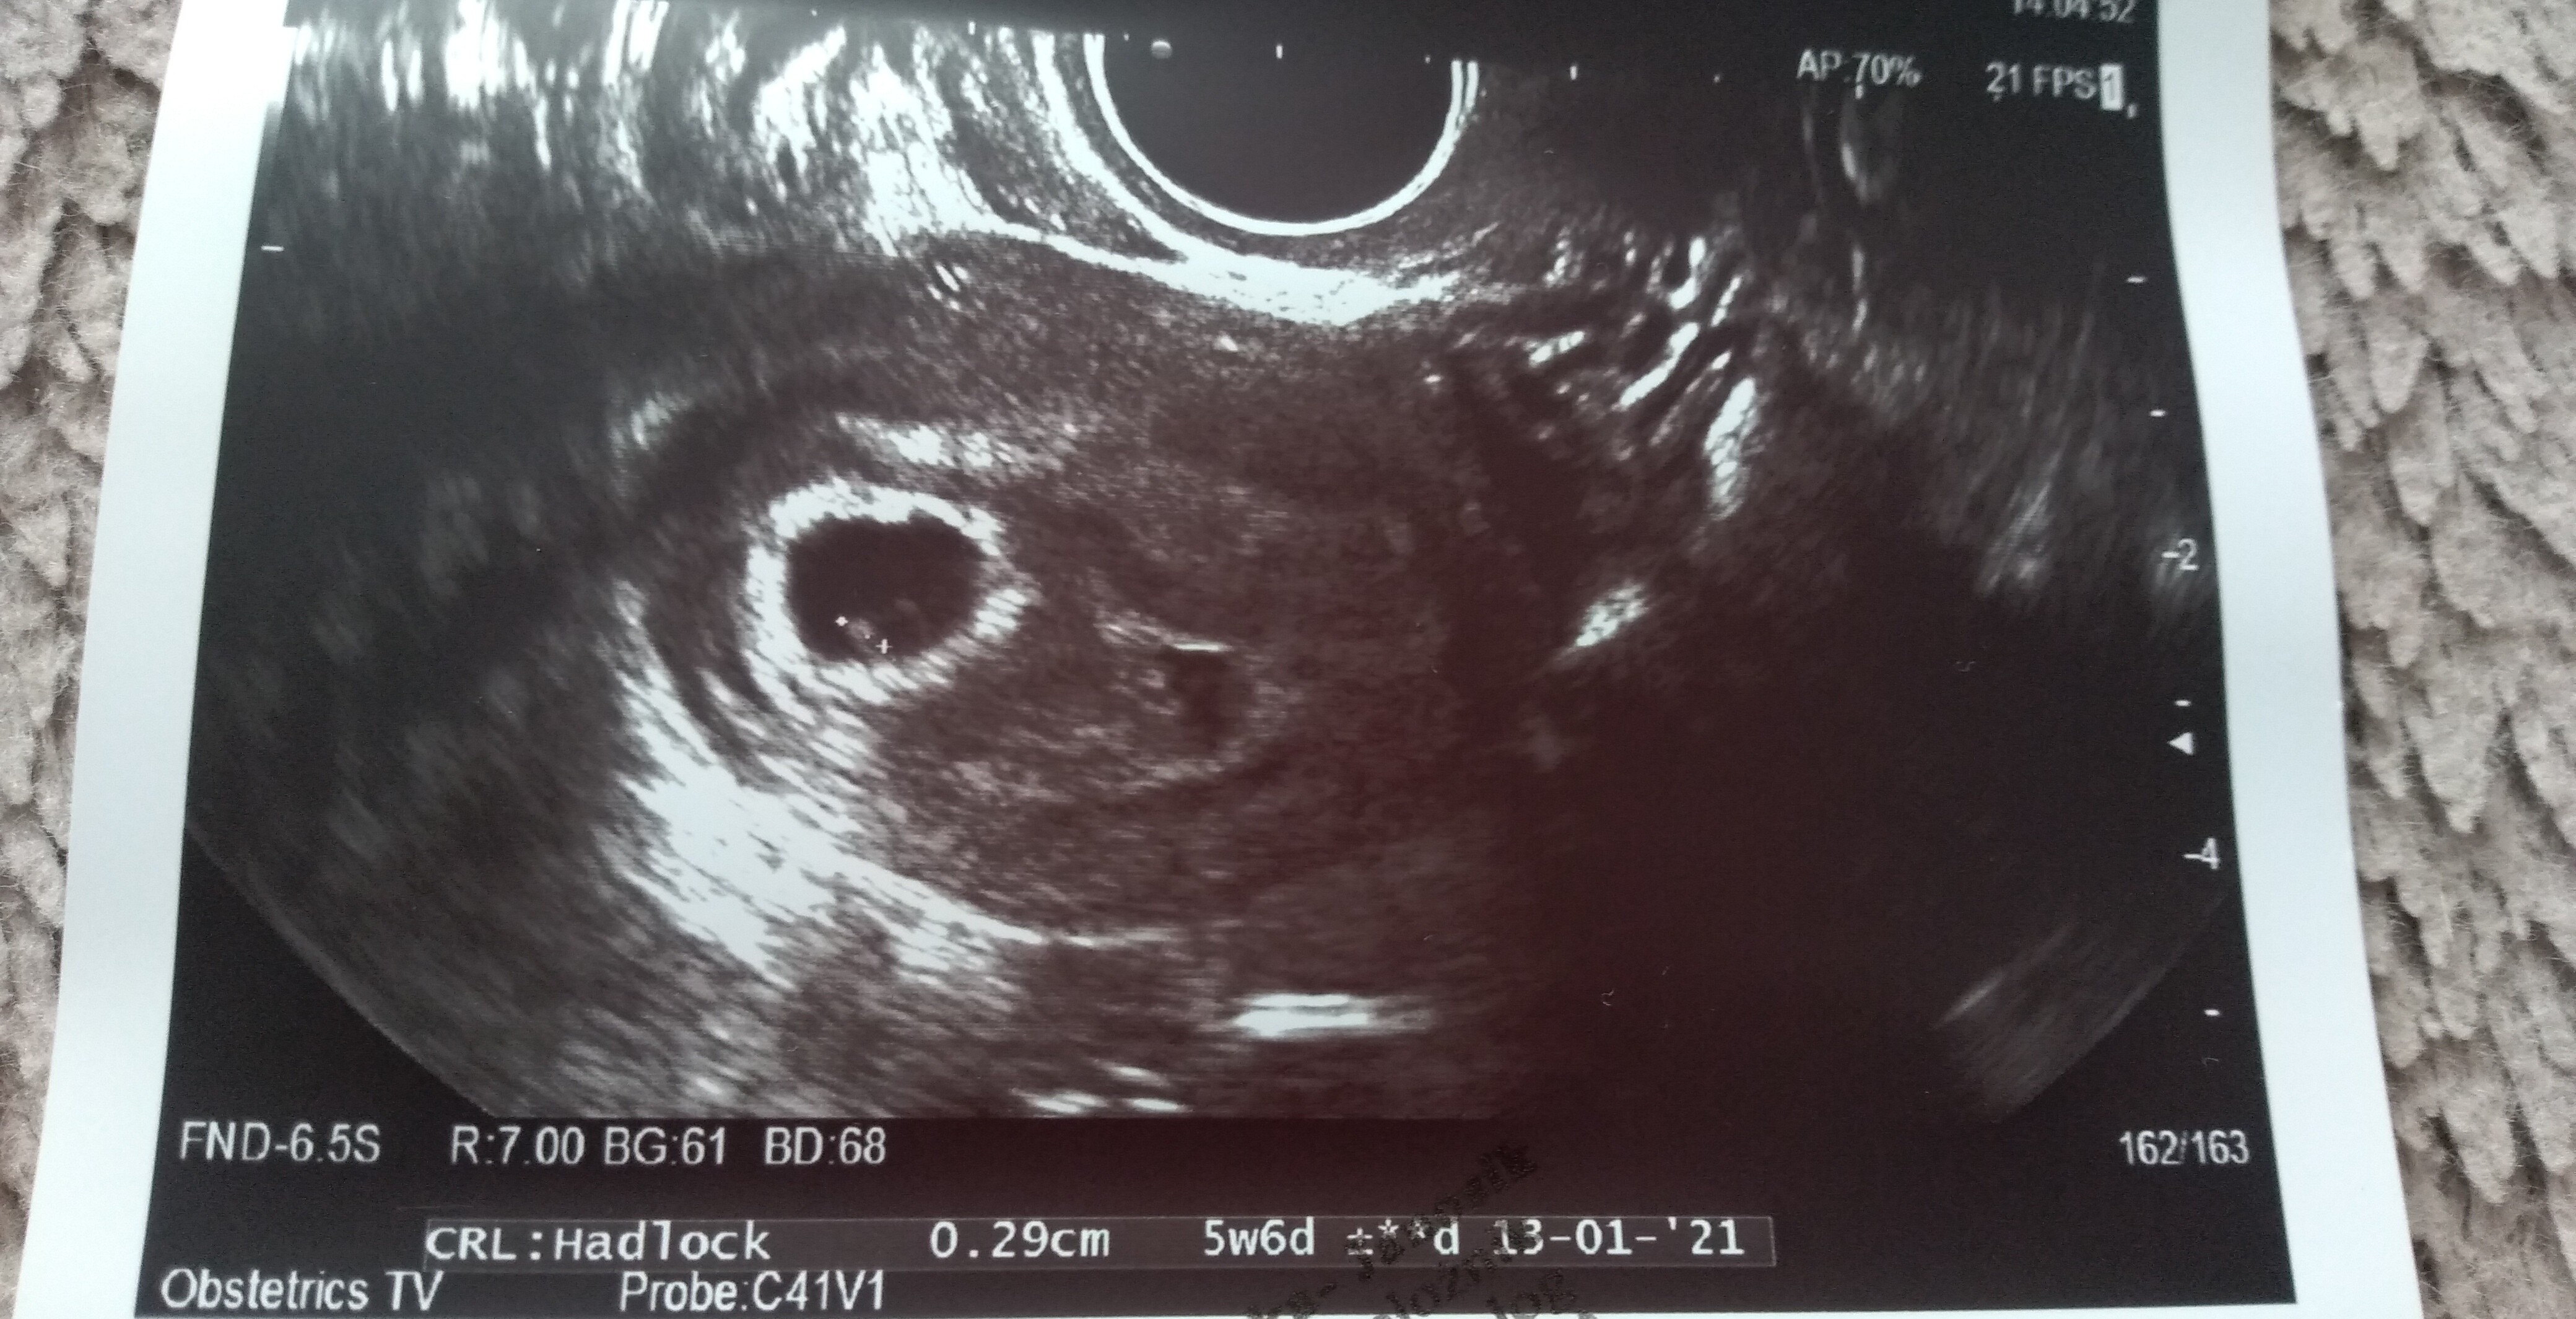

Hej kochana! Oszczędzaj się i dużo odpoczywaj ! ❤ mam nadzieję, że wszystko będzie dobrze i trzymam kciuki z całego serca! Na początku jeśli chodzi o pomiary mam wrażenie, że Zawsze są jakieś rozbieżności w Zależności od ustawienia parametrów oraz głowicy USG... Tak czy inaczej wierzę, że wszystko będzie dobrze!Hej dziewczyny, byłam na usg. Nie wiem co o tym myślećpowiedziała, że pęcherzyk ciążowy jest za mały na swój wiek. Ma 1,21 cm. Według aplikacji dziś 6+1

jest zarodek 2,9 mm. Serduszko bije 111/min. Nie puściła mi do słuchania tylko liczyła, widziałam jak faluje.

Jednak ciąża jakby jest młodsza o 2 tyg - usg pokazuje 4+2

Nie mogłam później zajść o 2 tyg bo tydzień temu na usg usłyszałam, że ciąża jest o 3 dni starsza. Poza tym robiłam betę 28 dc i już była pozytywna więc nie mogłam mieć wtedy owulacji.

Dodatkowo mam krwiaka większego dwa razy od pęcherzyka ciążowego - ma 8 na 5 i obok jakieś jeszcze mniejsze...

W razie krwawienia mam jechać na izbę przyjęć... Powiedziała, że ciąża wysokiego ryzyka, mam tylko leżeć. Karty ciąży nie założyła. Kontrola za 2 tyg. Dołożyła luteine i teraz mam 3 x1 duphaston, 2x1 luteina